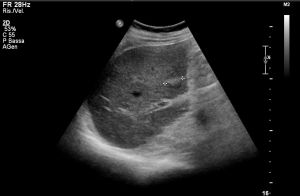

Ad oggi sono state identificate con l’ecografia addominale prevista dal protocollo, 9 neoplasie del parenchima epatico: 5 angiosarcomi (Fig. 1-4) (di cui 2 viventi) e 4 epatocarcinomi (Fig. 5-7) (di cui 1 vivente), successivamente sottoposte a studio TC e tutte confermate dalla diagnosi istologica.

Fig.3. Caso 2 di angiosarcoma epatico

Fig.4. Caso 2 di angiosarcoma epatico